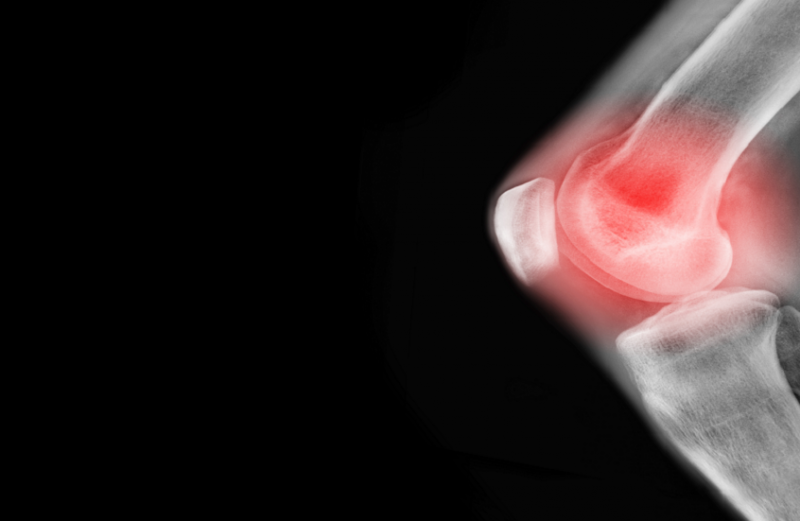

دراسة تؤكد فوائد تمارين اليوغا لعلاج آلام مفاصل الركبة

أظهرت دراسة أجراها باحثون أستراليون أن تمارين اليوغا لها أثر فعال في علاج آلام مفاصل الركبة.